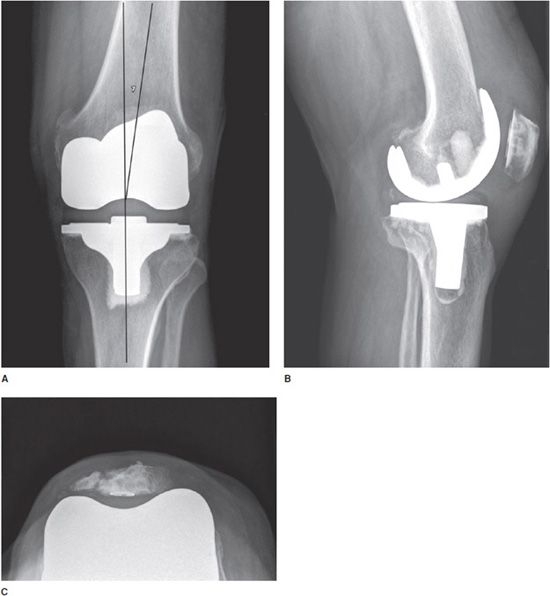

Case Study Custom Total Knee Replacement in Left Knee Arthritis with Knee Surgery Hardware Removal Please read these instructions completely and ask for clarification if. Here are 10 indications for hardware removal after fracture fixation: During the surgery, your surgeon may: Unpredictable results when removed solely for pain relief and even less so for function. In fact, many orthopedic surgeons describe hardware removal to new trainees and residents to be the most difficult procedure. in. Knee Surgery Hardware Removal.